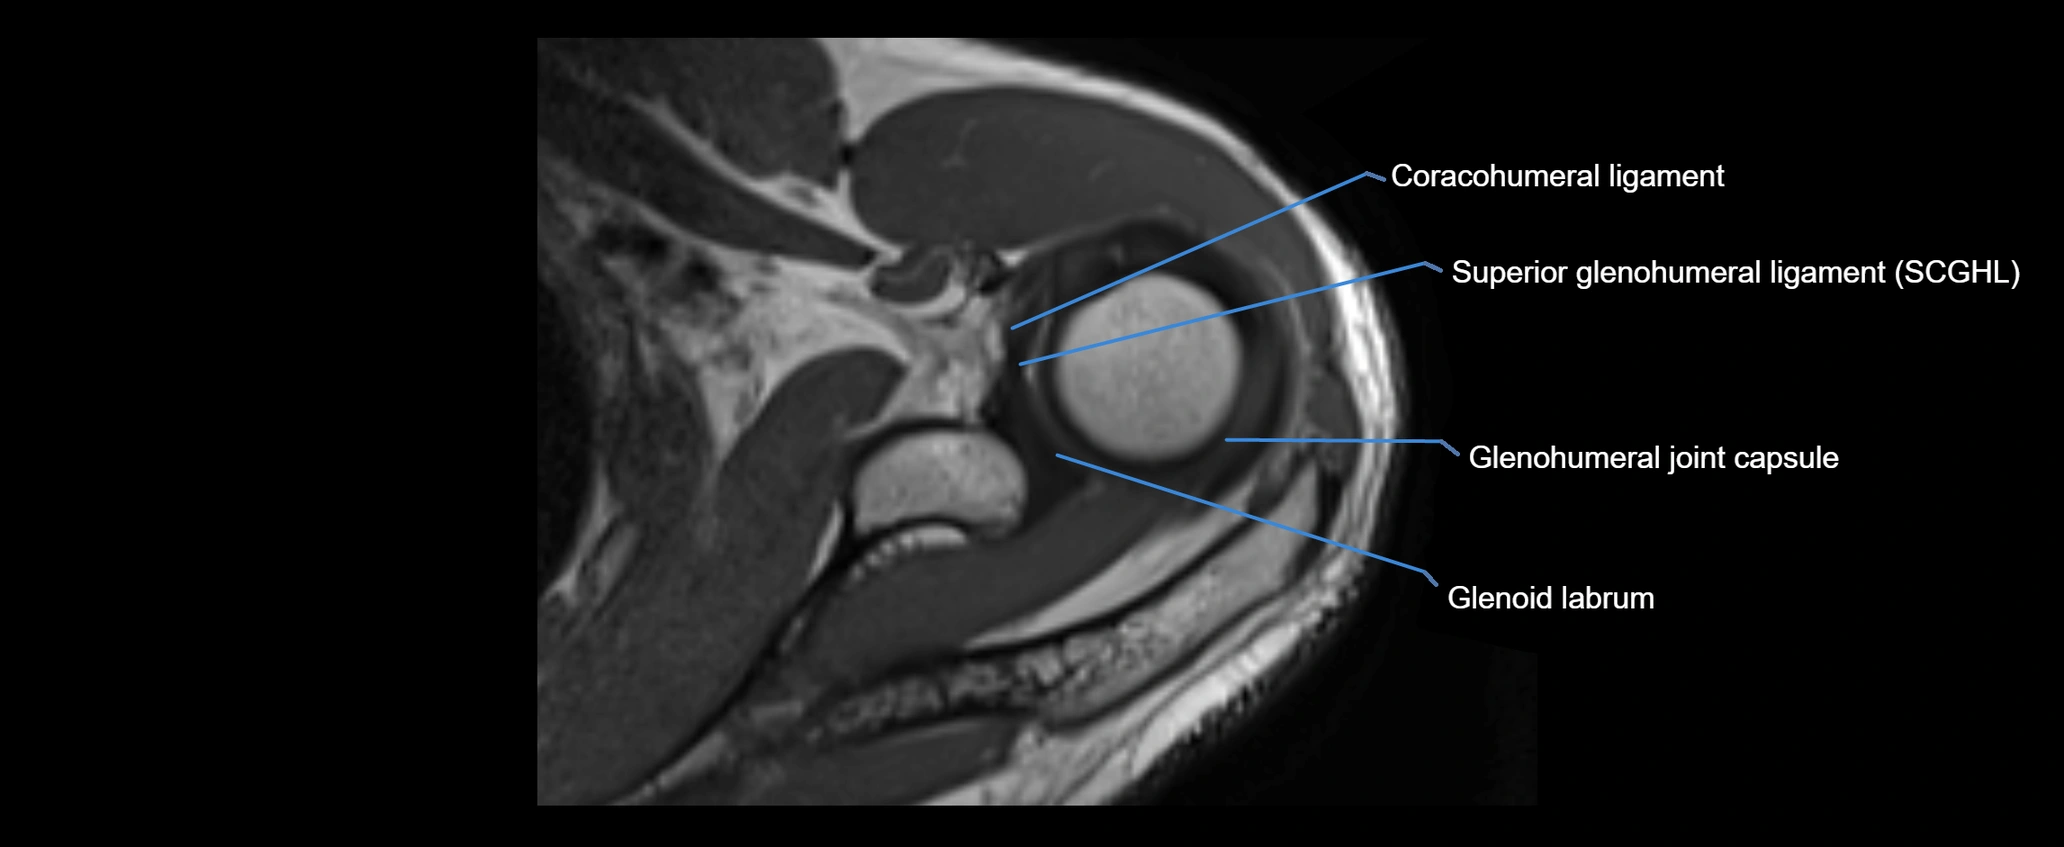

MRI images

image

MRI Appearance

• T1-weighted images:

• Normal ligament: Low signal (dark linear band) spanning acromion to clavicle.

• Surrounding fat planes: Bright, delineating the ligament clearly.

• T2-weighted images:

• Normal ligament: Low signal, homogeneous.

• Proton Density Fat-Saturated (PD FS):

• Normal ligament: Low signal, uniform thickness.